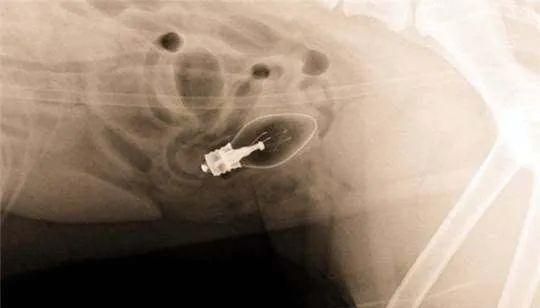

医生给Harvey拍了X光片后发现,这家伙的肚子里竟然装了满满一肚子的袜子。

经过4个小时的紧急抢救,Harvey总算是脱离了危险。